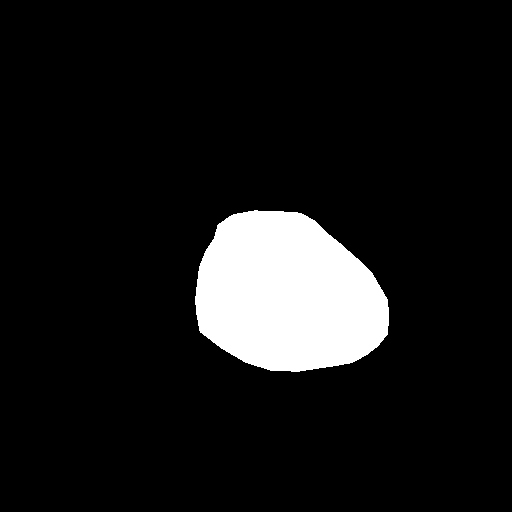

3.4 Postprocessing

After heart and lung masks are computed, we performed dilation followed by erosion to fill holes in output mask [18], then we find the connected components of prediction masks (Figure 3).

From the lung mask, we chose the two largest connected components and disregarded others as noise. The connected component with a lower x-axis coordinate is designated as the left lung mask and the other as the right lung mask. From the heart mask, we chose the connected component larger than a given threshold and closest to the center and designate it as the heart mask.